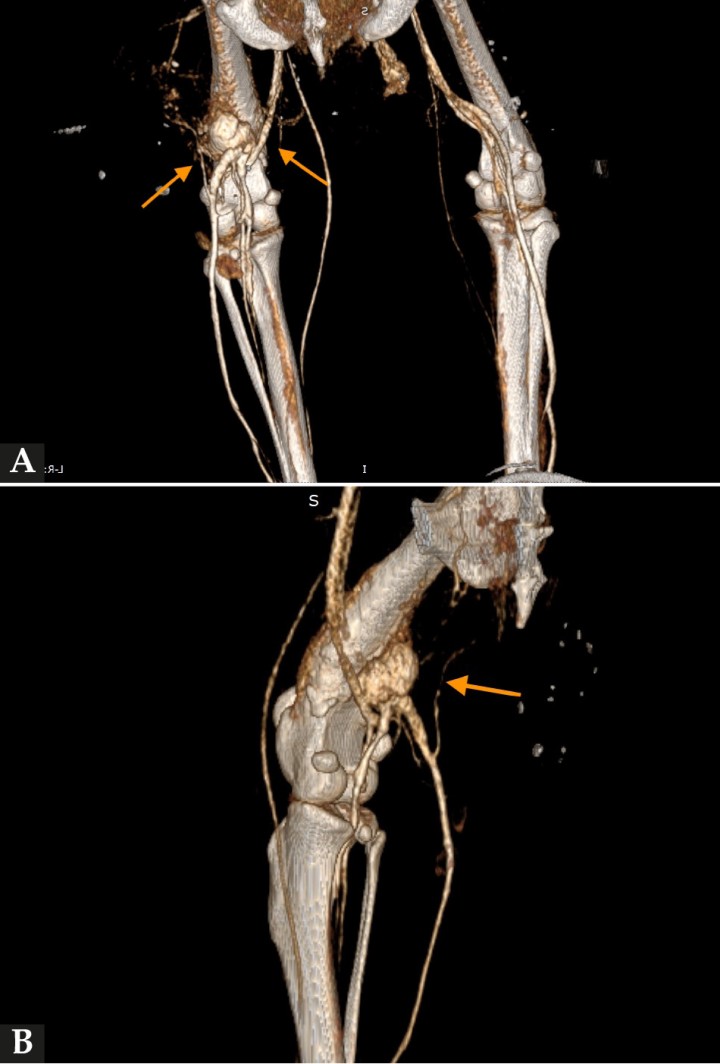

En la diáfisis media y metáfisis distal del fémur derecho, se visualizó una lesión ósea con características agresivas (Fig. 1). Presentaba un aumento de atenuación de la cavidad medular del hueso, heterogénea, y una reacción perióstica sólida y con “borde de cepillo” que rodeaba de forma concéntrica el fémur. Esta lesión era compatible con un proceso neoplásico óseo primario o metastático (osteosarcoma o sarcoma histiocítico), o con un proceso infeccioso (fúngico o menos probablemente otros como leishmaniosis o hepatozoonosis). En la cortical laterocaudal, se observó un defecto óseo con márgenes bien definidos, probablemente producido por la biopsia descrita en la historia.

<p>(<strong>A</strong>) Imagen de TC en ventana hueso en un corte transversal. En la sección femoral de la extremidad pelviana derecha se observa una lesión agresiva con reacción perióstica y aumento de la atenuación medular. Se aprecia asimismo un defecto cortical presumiblemente causado por la biopsia ósea realizada previamente. (<strong>B</strong>) Imagen de TC en ventana hueso reconstruida en plano dorsal. En el fémur derecho se visualizan las lesiones óseas descritas en (<strong>A</strong>). (<strong>C</strong>) Imagen de TC en ventana hueso reconstruida en plano sagital. Se observa la lesión ósea de características agresivas y el defecto cortical descrito en (<strong>A</strong>). Caudodistalmente al defecto óseo provocado presumiblemente durante la biopsia, se intuye una estructura redondeada ligeramente hiperatenuante respecto a los tejidos adyacentes compatible con el pseudoaneurisma descrito en este caso.</p>

Figura 1

(A) Imagen de TC en ventana hueso en un corte transversal. En la sección femoral de la extremidad pelviana derecha se observa una lesión agresiva con reacción perióstica y aumento de la atenuación medular. Se aprecia asimismo un defecto cortical presumiblemente causado por la biopsia ósea realizada previamente. (B) Imagen de TC en ventana hueso reconstruida en plano dorsal. En el fémur derecho se visualizan las lesiones óseas descritas en (A). (C) Imagen de TC en ventana hueso reconstruida en plano sagital. Se observa la lesión ósea de características agresivas y el defecto cortical descrito en (A). Caudodistalmente al defecto óseo provocado presumiblemente durante la biopsia, se intuye una estructura redondeada ligeramente hiperatenuante respecto a los tejidos adyacentes compatible con el pseudoaneurisma descrito en este caso.